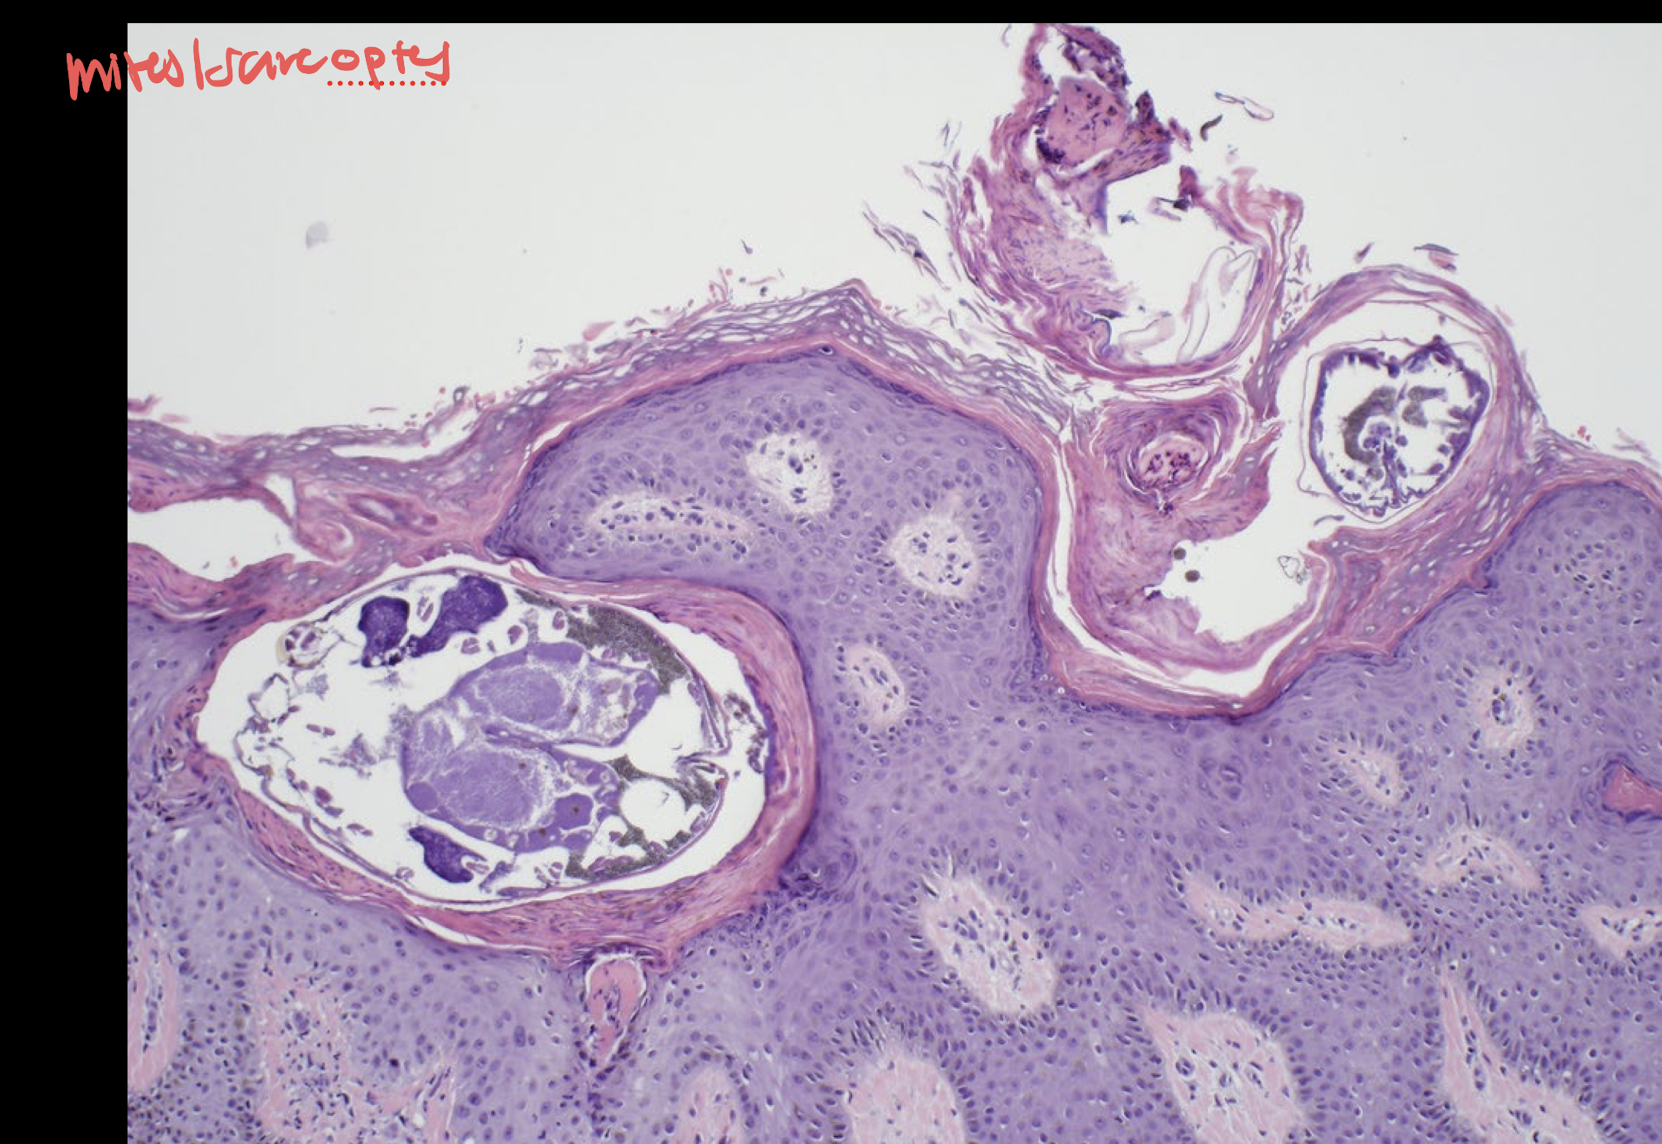

demodicosis

no inflammation bc they are within the hair follicles unless they rupture